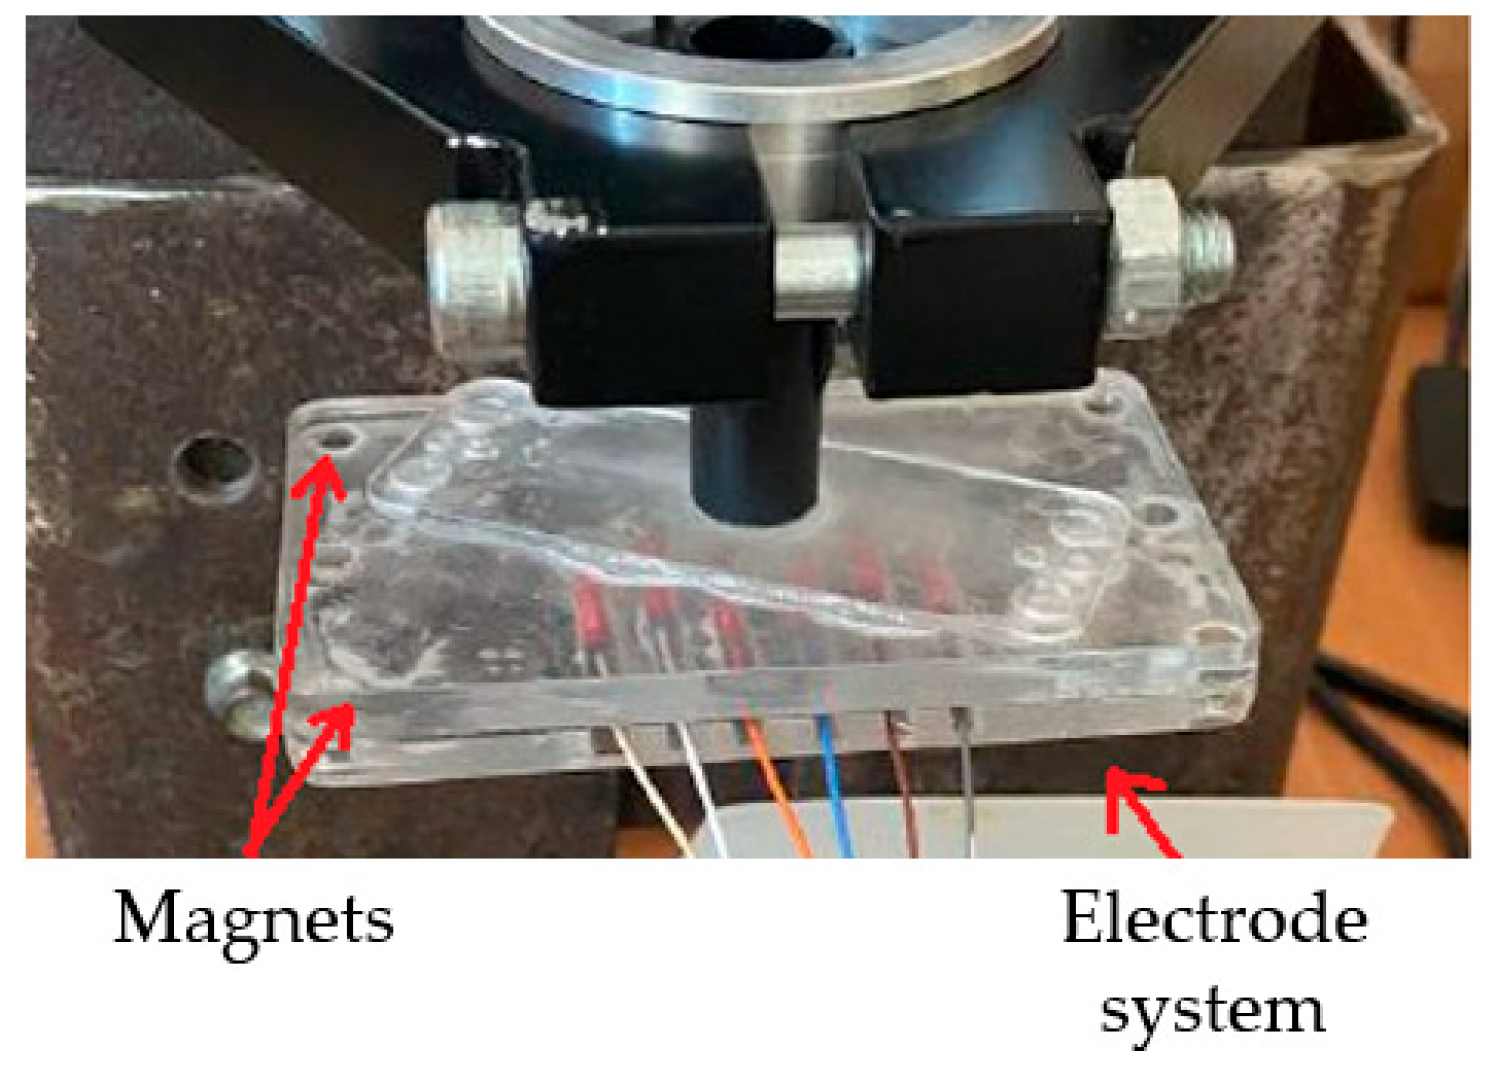

2.5. Laboratory Facilities Diagram

2.6. Measurement Design